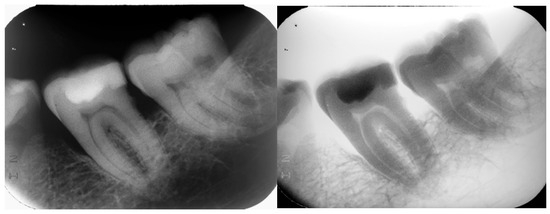

Background: Class II Division 1 malocclusion is often characterized by an increased overjet, which has traditionally been considered a negative predictor of aesthetic outcomes, treatment efficacy, and long-term stability. Although early two-phase tre...